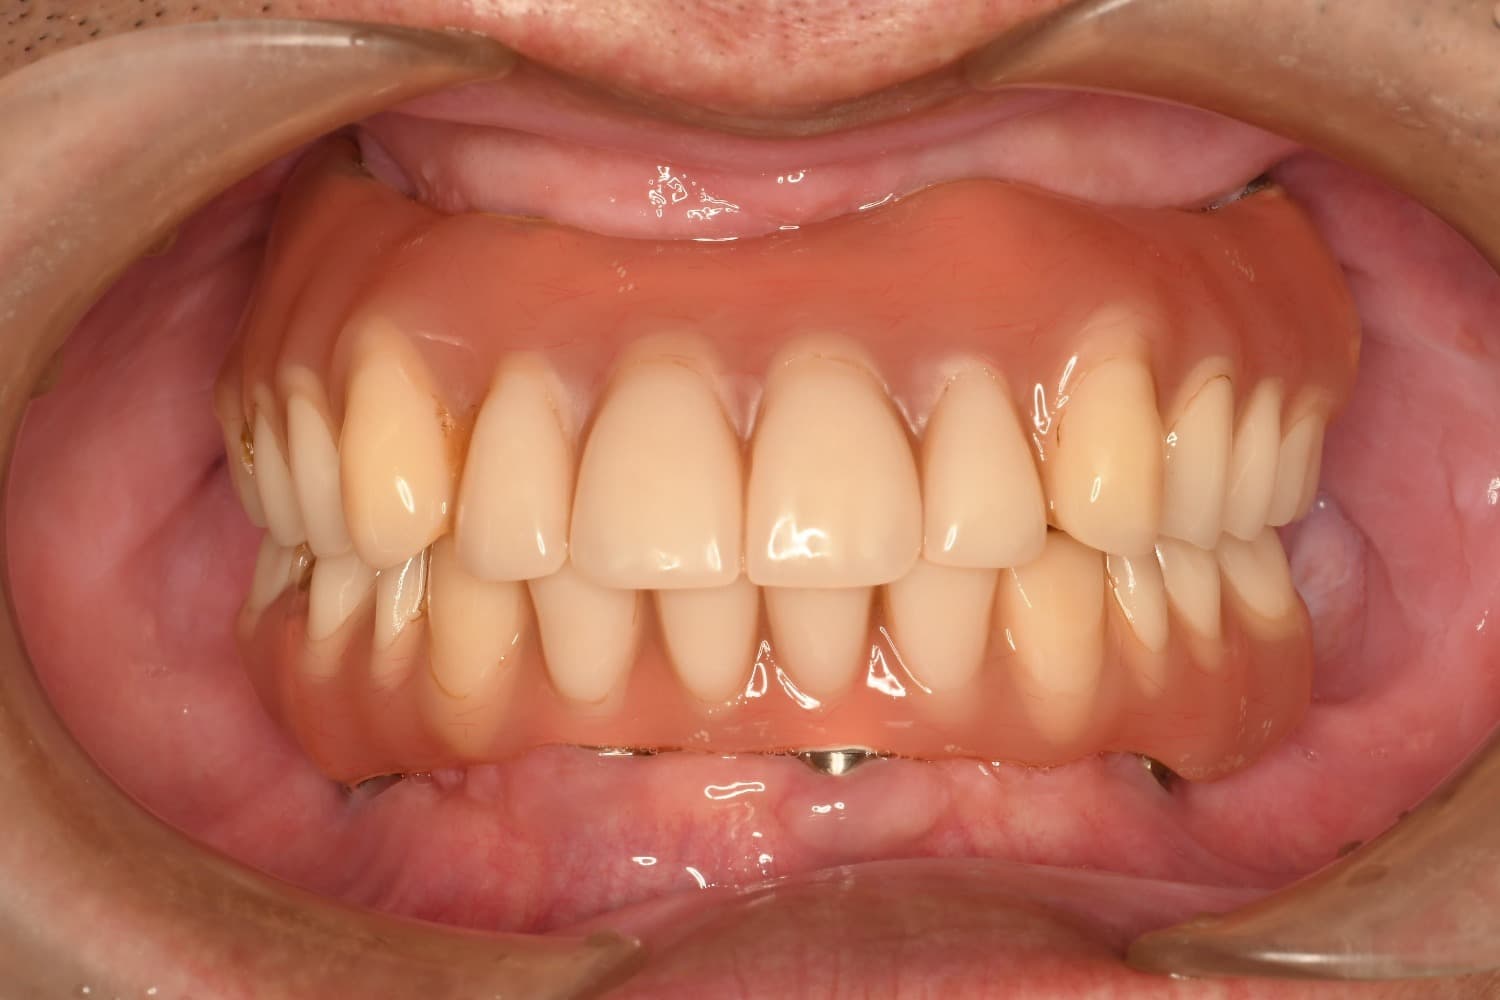

全歯のインプラント治療(50代/男性)

After

オールオン4

年齢

50代

性別

男性

主訴

他院で総義歯を入れたが、噛むと上の義歯が落ちて使えない。インプラント相談希望。

治療期間

10カ月

治療回数

12回

費用

6,000,000円+骨造成代

副作用・リスク

メインテナンスが出来ていないとインプラント周囲炎になる。よく噛めるため、上部構造が使用していくうちに破損することがある。